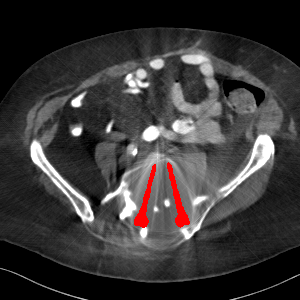

Visual comparison. As shown in Fig. 5, metallic implants such as spinal rods and hip prosthesis cause severe streaky artifacts and metal shadows, which obscure bone structures around them. cGan-CT cannot recover image intensity correctly for both cases. Sinogram domain or dual-domain methods perform much better than cGan-CT. LI, NMAR, and CNNMAR introduce strong secondary artifacts and distort the whole images. In NMAR images, there are fake bone structures around the metals, which is related to segmentation error in the prior image from strong metal artifacts. The segmentation error is also visible in NMAR sinogram. CNNMAR cannot restore the correct bone structures between rods in case 1. The tissues around the metals are over-smoothed in DuDoNet because LI sinogram and image are used as inputs, and the missing information cannot be inferred later. Our model retains more structural information than DuDoNet and generates anatomically more faithful artifact-reduced images.

Visual comparison. Fig. 7 shows two clinical CT images with metal artifacts. Case 1 is with moderate metal artifacts. cGan-CT does not suppress the artifacts completely and generates some fake details. LI, NMAR, CNN-MAR remove all the artifacts but introduce new streak artifacts, which is caused by the discontinuity in the corrected sinogram. DuDoNet outputs over-smoothed sinogram, which leads to blurred tissues close to the metal implants, such as muscle and bone. Only our model can provide realistic enhanced sinogram and remove the artifacts while retaining the structure of nearby tissues. Case 2 is very challenging as the rods bring strong metal shadows and bright artifacts around the vertebra. cGan-CT recovers the shape of vertebra but changes the overall image intensity. Other sinogram inpainting methods fail as the soft tissue and bone near the rods are heavily distorted. Our model removes part of the dark bands and reproduces correct anatomical structures around the rods.